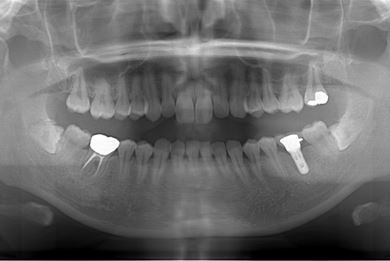

| 性別/年齢 | 女性 / 30歳 | ||||||||||||||||||||||||||||||||

| 主訴 | 銀歯がはずれた奥歯にひびが入っており、抜歯しなければいけないため、インプラントの治療相談を希望。 | ||||||||||||||||||||||||||||||||

| 治療内容 | インプラント1本、メタルボンドセラミック1本 | ||||||||||||||||||||||||||||||||

| 総治療費 | 401,363円 | ||||||||||||||||||||||||||||||||

| 治療期間 | 5ヶ月 |